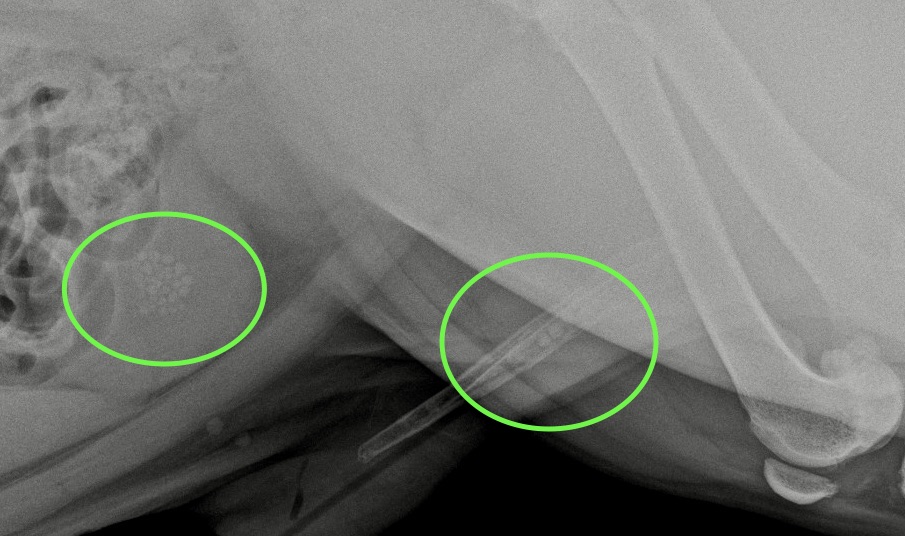

Retrait de lithiases vésicales par technique mini-invasive